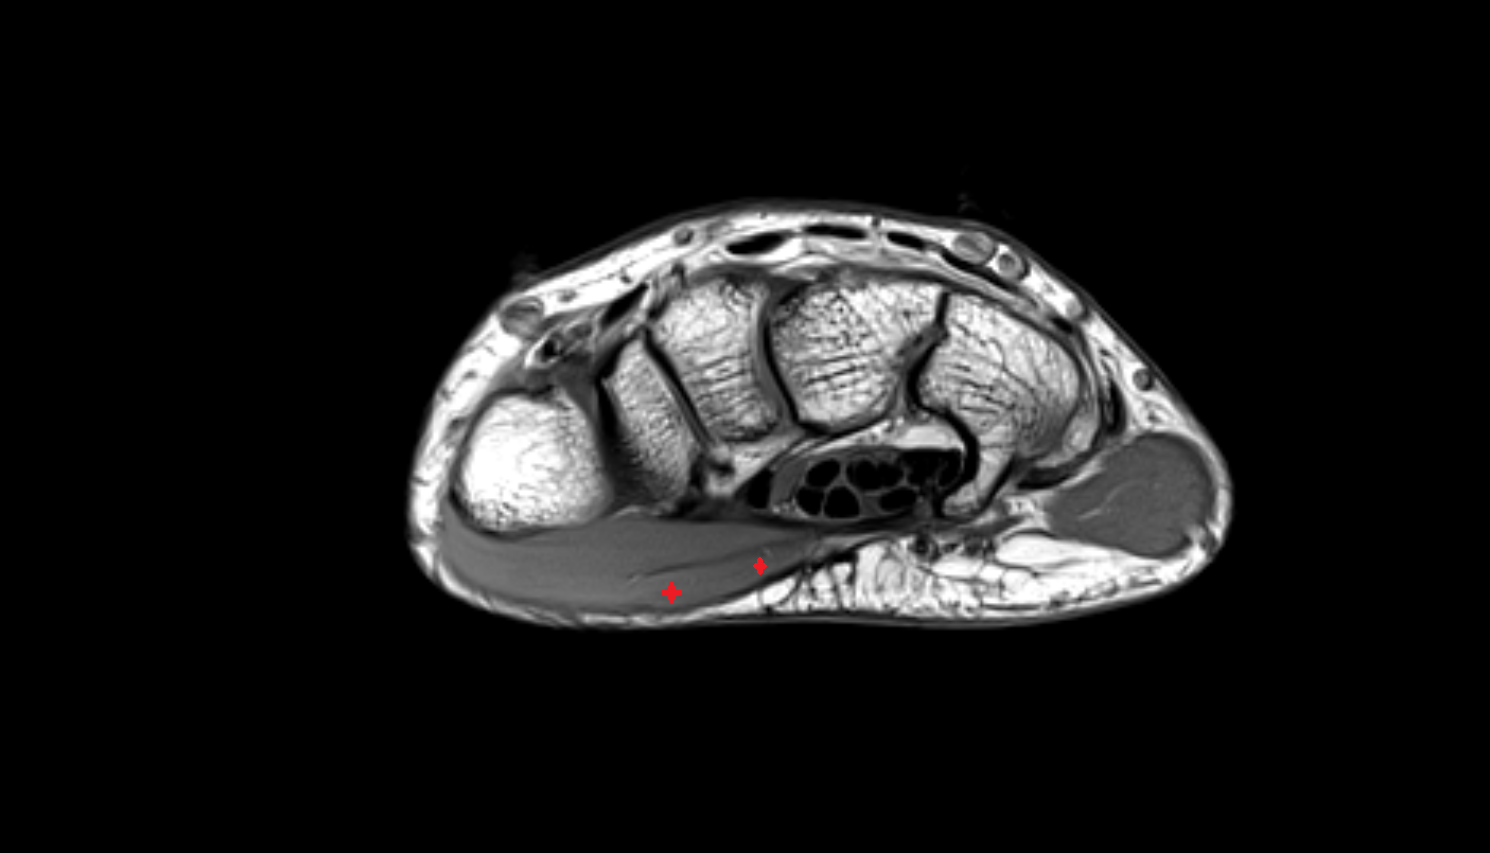

- Plantar aponeurosis